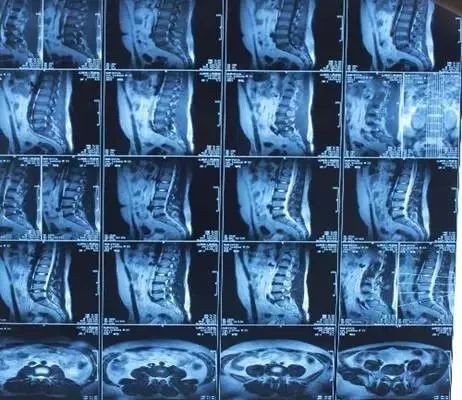

磁共振(MRI)就是常说的核磁,因为名字里带个核字,大家老误解它可能有放射线和辐射,其实这个核指的是氢原子核。

核磁共振机使用较强大的磁场,使人体中所有水分子磁场的磁力线方向一致,这时磁共振机的磁场突然消失,身体中水分子的磁力线方向,突然恢复到原来随意排列的状态。反复多次施加磁场又突然消失,核磁共振机会得到充分的数据并运算后成像。

磁共振是人造了一个磁场,利用电磁波信号成像,没有放射线,对人体没有辐射也没有伤害。所以,核磁没有辐射!

磁共振可以检查的部位很多,包括脑部、血管、肌肉、韧带、脊柱等等,但是建议在有症状或医生建议下做磁共振检查,正常的体检作为疾病的初期筛查,通常没有必要做磁共振。